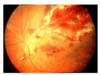

Qual a clínica da necrose aguda de retina?

Retinite necrosante periférica, confluentes cincunferencialmente.

Vitreíte, vasculite, neurite e reação de câmara anterior intensas são observadas. A uveíte anterior associada pode ser granulomatosa.

Qual a característica da forma clássica ou hemorrágia da retinite por CMV?

Lesões branco/amareladas confluentes, associadas a hemorragias retinianas e embainhamento vascular, com distribuição segmentar (aspecto em “queijo com Ketchup”)

Sem vitreíte